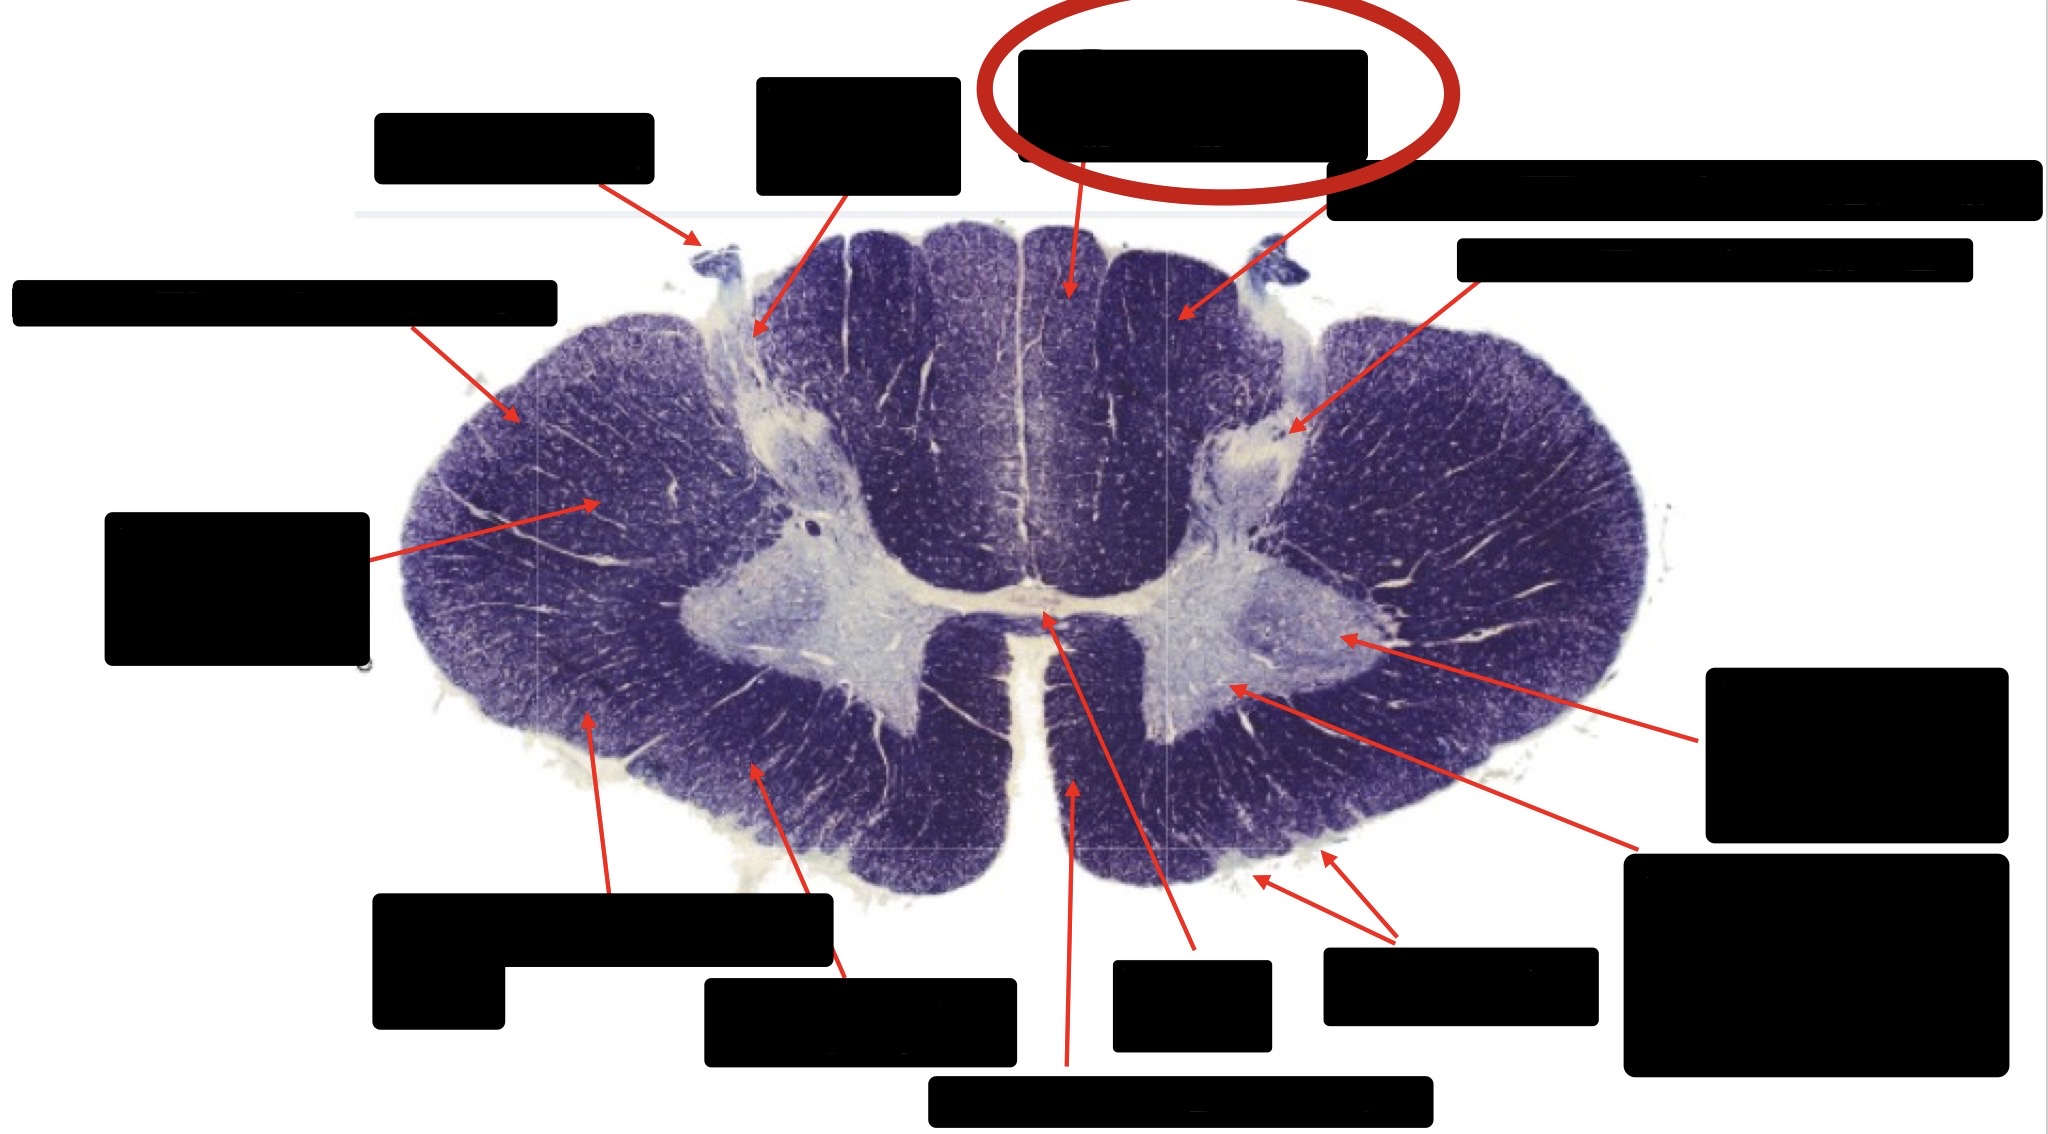

Central Canal

Posterior Column (Fasciculus Gracilis)

Large Fiber Entry Zone

Lissaeur’s Tract & Small Fiber Entry Zone

Substantia Gelatinosa

Lateral Corticospinal Tract

Ventral Root Fibers

Anterior Horn Motor Neurons

Anterior Medial Fissure

Dorsal Rootlet

Posterior Spinocerebellar Tract

Anterior Spinocerebellar Tract

Spinothalmic Tract

Posterior Column (Fasciculus Cuneatus)

Anterior Horn Motor Neurons (Distal Muscles)

Anterior Horn Motor Neurons (Proximal Muscles)

Anterior Corticospinal Tract